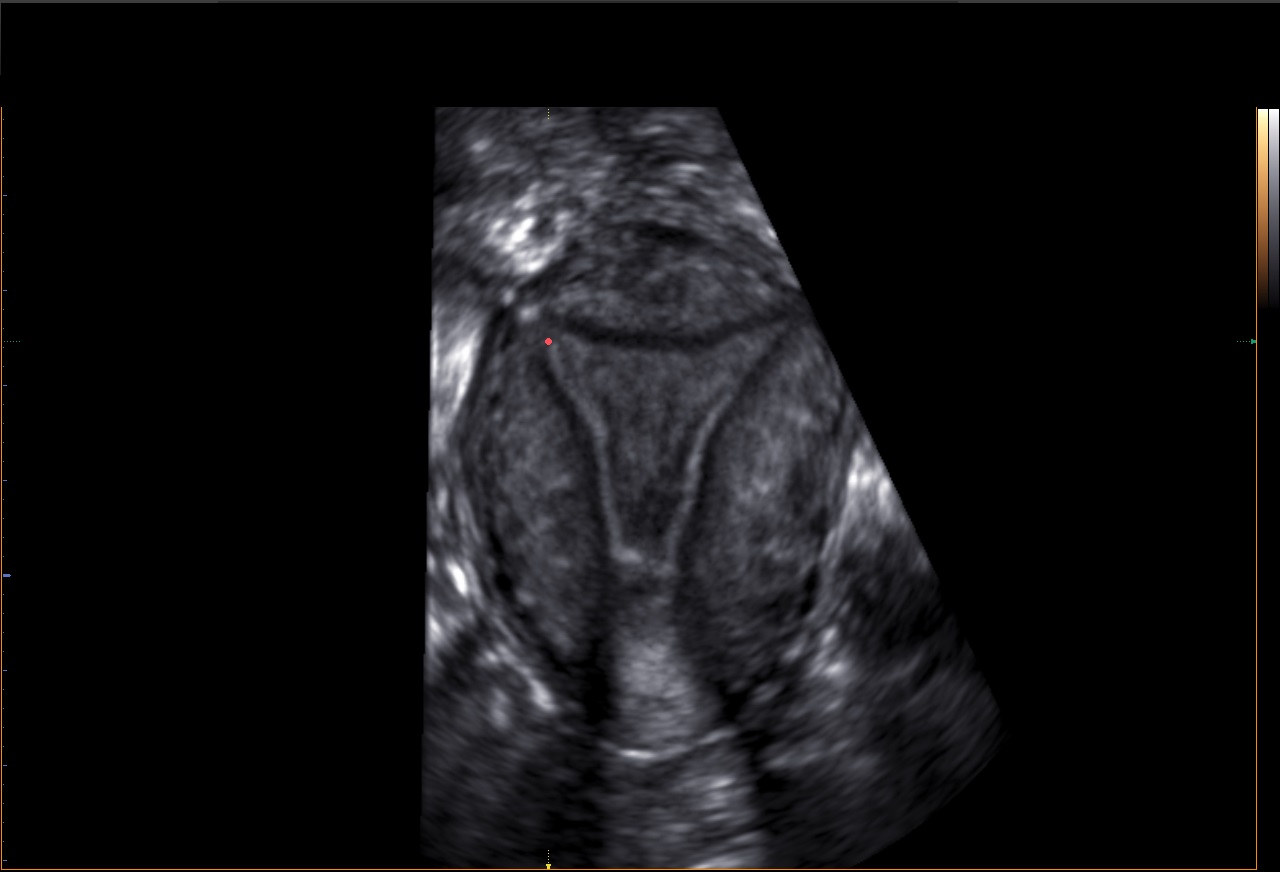

Le BiometryAssist™ est une technologie de biométries semi-automatisées qui permet à l'utilisateur de gagner en efficacité et en productivité.